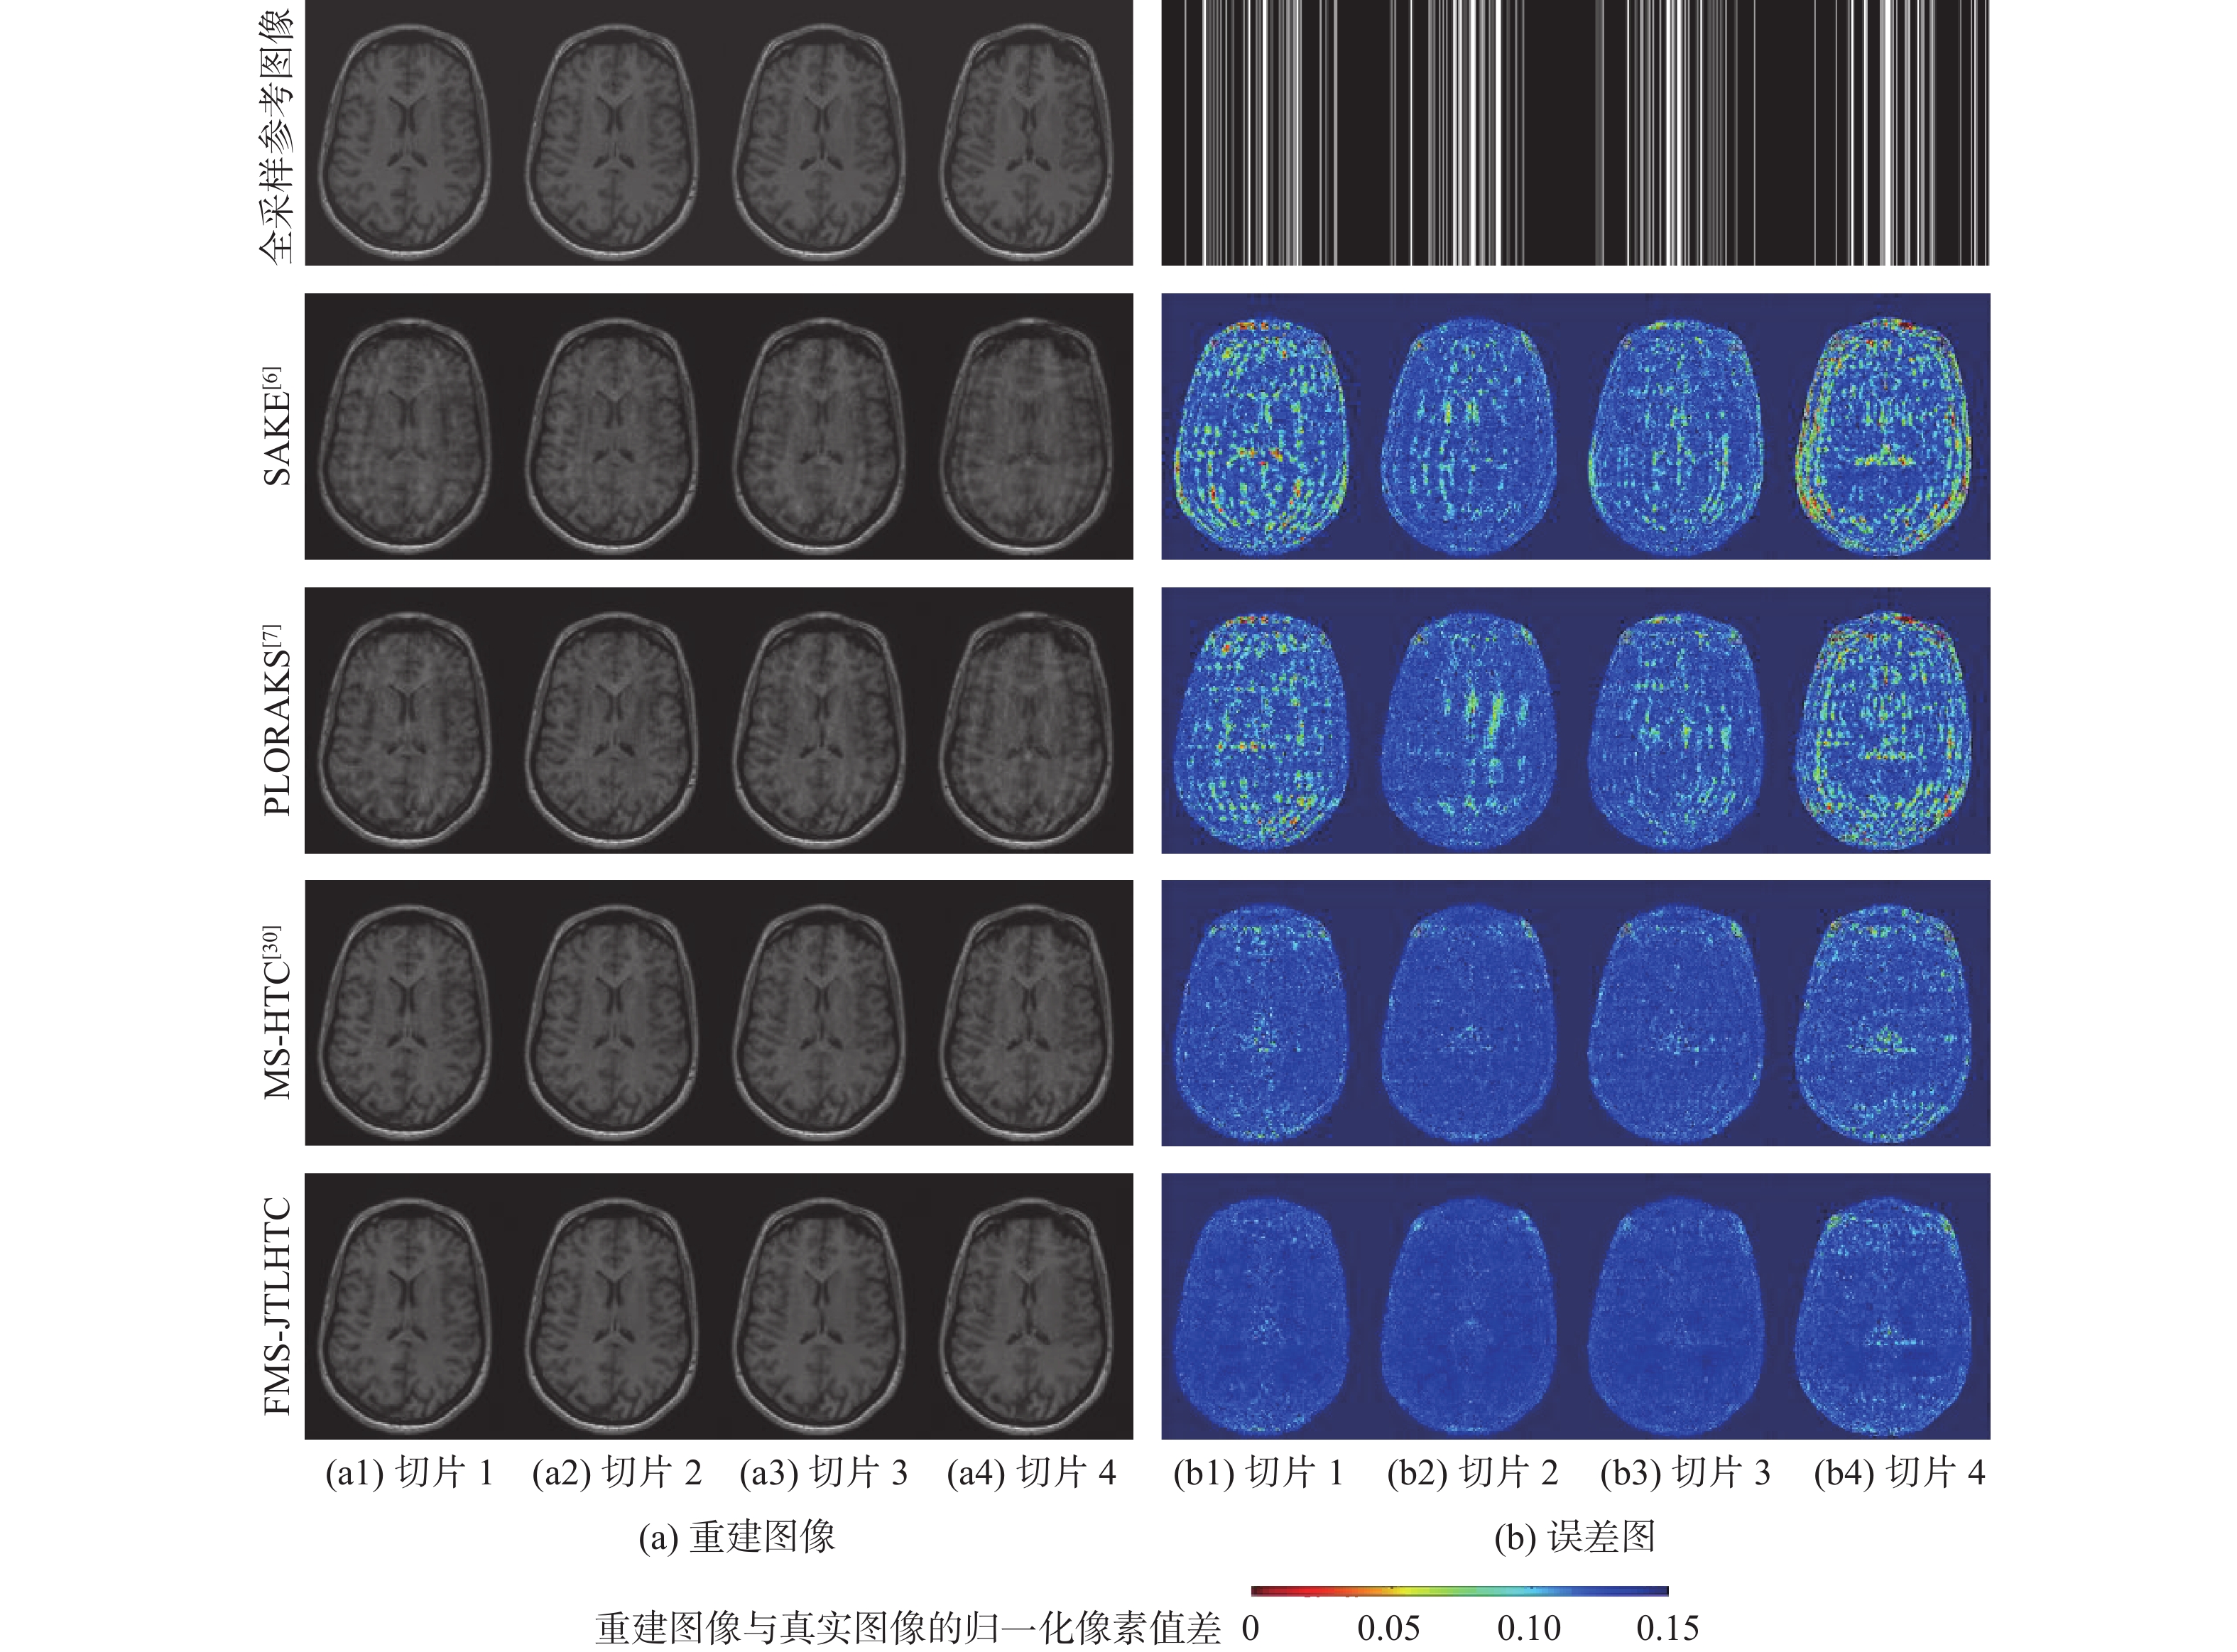

二维(2D)多切片磁共振数据在相邻切片之间具有高度的相关性,通过利用切片间的冗余性能够重建出更高质量的切片图像,但由于硬件条件的限制,2D多切片磁共振成像(MRI)需要耗费大量时间。为提高2D多切片磁共振图像的重建质量和重建速度,将联合稀疏变换学习正则项引入到多切片Hankel张量完成(MS-HTC)模型中,提出一种快速2D多切片磁共振成像重建(FMS-JTLHTC)算法。该算法使用交替方向乘子法对目标问题进行求解;引入快速迭代收缩阈值法加快收敛,并使用图形处理器对算法进行加速。使用4组脑部数据集在2种不同采样模式下进行实验,结果表明:FMS-JTLHTC算法的峰值信噪比(PSNR)相较于同时自动校准和K空间估计(SAKE)算法、并行成像数据的局部K空间领域的低秩建模(PLORAKS)算法和MS-HTC算法分别平均提高了4.04 dB、3.67 dB和2.07 dB,而且重建速度相比MS-HTC算法提高了14倍。

Abstract:Due to the significant correlation between neighboring slices in two-dimensional (2D) multi-slice magnetic resonance data, higher quality slice pictures can be reconstructed by taking use of the redundancy between slices. However, 2D multi-slice magnetic resonance imaging requires an amount of time. To improve the reconstruction quality and speed of 2D multi-slice (MRI) images, proposes a fast 2D multi-slice MRI reconstruction (FMS-JTLHTC) algorithm, which introduces the joint transform learning regular term into the multi-slice hankel tensor completion (MS-HTC) model. Prior to introducing the fast iterative shrinkage-thresholding procedure to accelerate convergence and utilize the graphics processing unit to speed up the procedure, the alternating direction method of multipliers is used to solve the objective issue. Experiments using four brain datasets in two different sampling modes show that the peak signal-to-noise ratio (PSNR) of the FMS-JTLHTC algorithm is improved by an average of 4.04 dB, 3.67 dB, and 2.07 dB compared to the simultaneous atuo-calibrating and K-space estimation (SAKE), low-rank modeling of local K-space neighborhoods with parallel imaging data (PLORAKS) and MS-HTC algorithms, respectively, the reconstruction speed is improved by a factor of 14 compared to the MS-HTC algorithm.